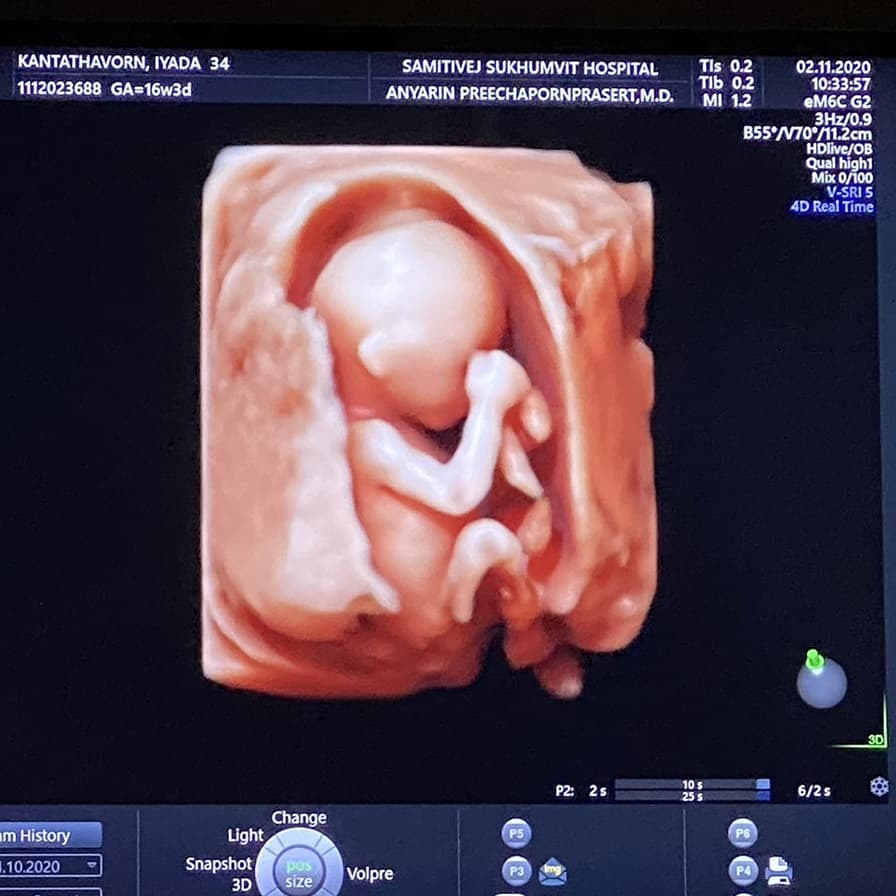

ล่าสุด (5 พฤศจิกายน 2563) คุณแม่พลอย ก็ได้โพสต์ภาพอัลตราซาวด์เบบี๋น้อยฉบับอัปเดต 16 สัปดาห์ แต่รอบนี้มาแบบ 4 มิติเลยล่ะ เผยให้เห็นภาพทารกน้อยแบบชัดเจน แขน ขา มือ มาครบ พร้อมข้อความว่า "บันทึก #16weekspregnant นน. หนูประมาณ 1.5 ขีด ความยาวตัวประมาณ 11 cm ประมาณมันฝรั่งลูกนึงได้ จิ๋ว ๆ กำลังโต อวัยวะหนูเริ่มมาชัดขึ้นมากเลยน้าาา หู แขน ขา มือ เท้า หัวใจ สมอง

อัลตราซาวด์ครั้งนี้เห็นไปยันกระเพาะปัสสาวะเลย คุณหมอบอกเห็นครบสุด ๆ ดิ้นหมุนตัวไป ๆ มา ๆ ตลอด แข็งแรงมากลูกหม่ามี๊ รักหนูที่สุดเลย กำลังใจน้อย ๆ ของหม่ามี๊ หม่ามี๊จะกินเยอะ ๆ นอนเยอะ ๆ เผื่อหนูน้าาา @kanploiandthebaby #kanploiandthebaby"